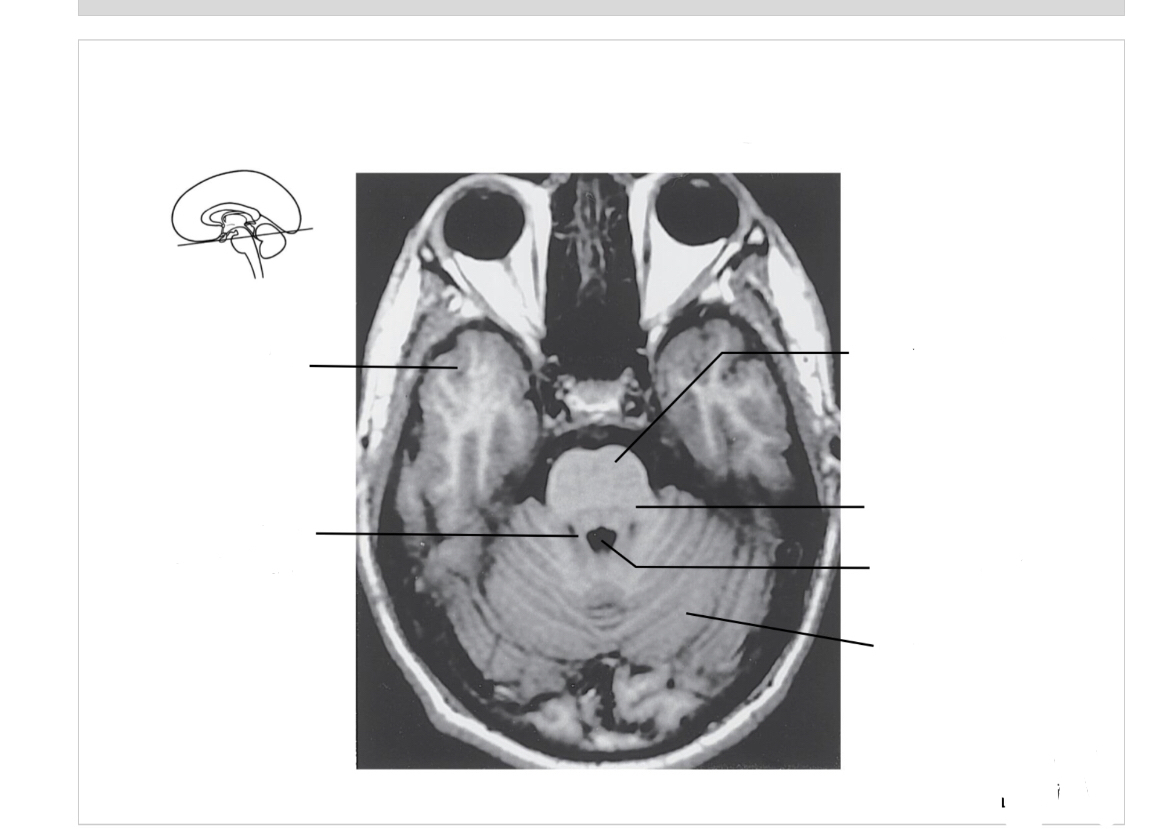

The structure indicated by the red line is? BONUS: SYMPTOMS IF THERE IS A LESION

motor spatial and directed movements (role in parkinsons?)

Bonus: Split Brain. L and R can’t communicate. Remember the test he did in class where he made us wave? Diagnose like that b/c wernickes is on left side so you cant wave ur left

motor problems